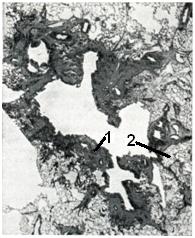

Стенки абсцесса в ранней стадии его формирования покрыты гнойно-фибринозными наложениями и обрывками некротизированных тканей. В дальнейшем по периферии абсцесса развивается зона демаркационного воспаления, составляющий ее инфильтрат служит основой для формирования пиогенной мембраны, образующей стенку полости (рис. 1). Пиогенная мембрана представляет собой богатый сосудами слой грануляционной ткани. Постепенно в той ее части, которая обращена в сторону окружающих абсцесса тканей, происходит созревание грануляций. Таким образом, если абсцесс приобретает хроническое течение, в пиогенной мембране образуются два слоя: внутренний, обращенный в полость и состоящий из грануляций, и наружный, образованный зрелой соединительной тканью (рис. 2).